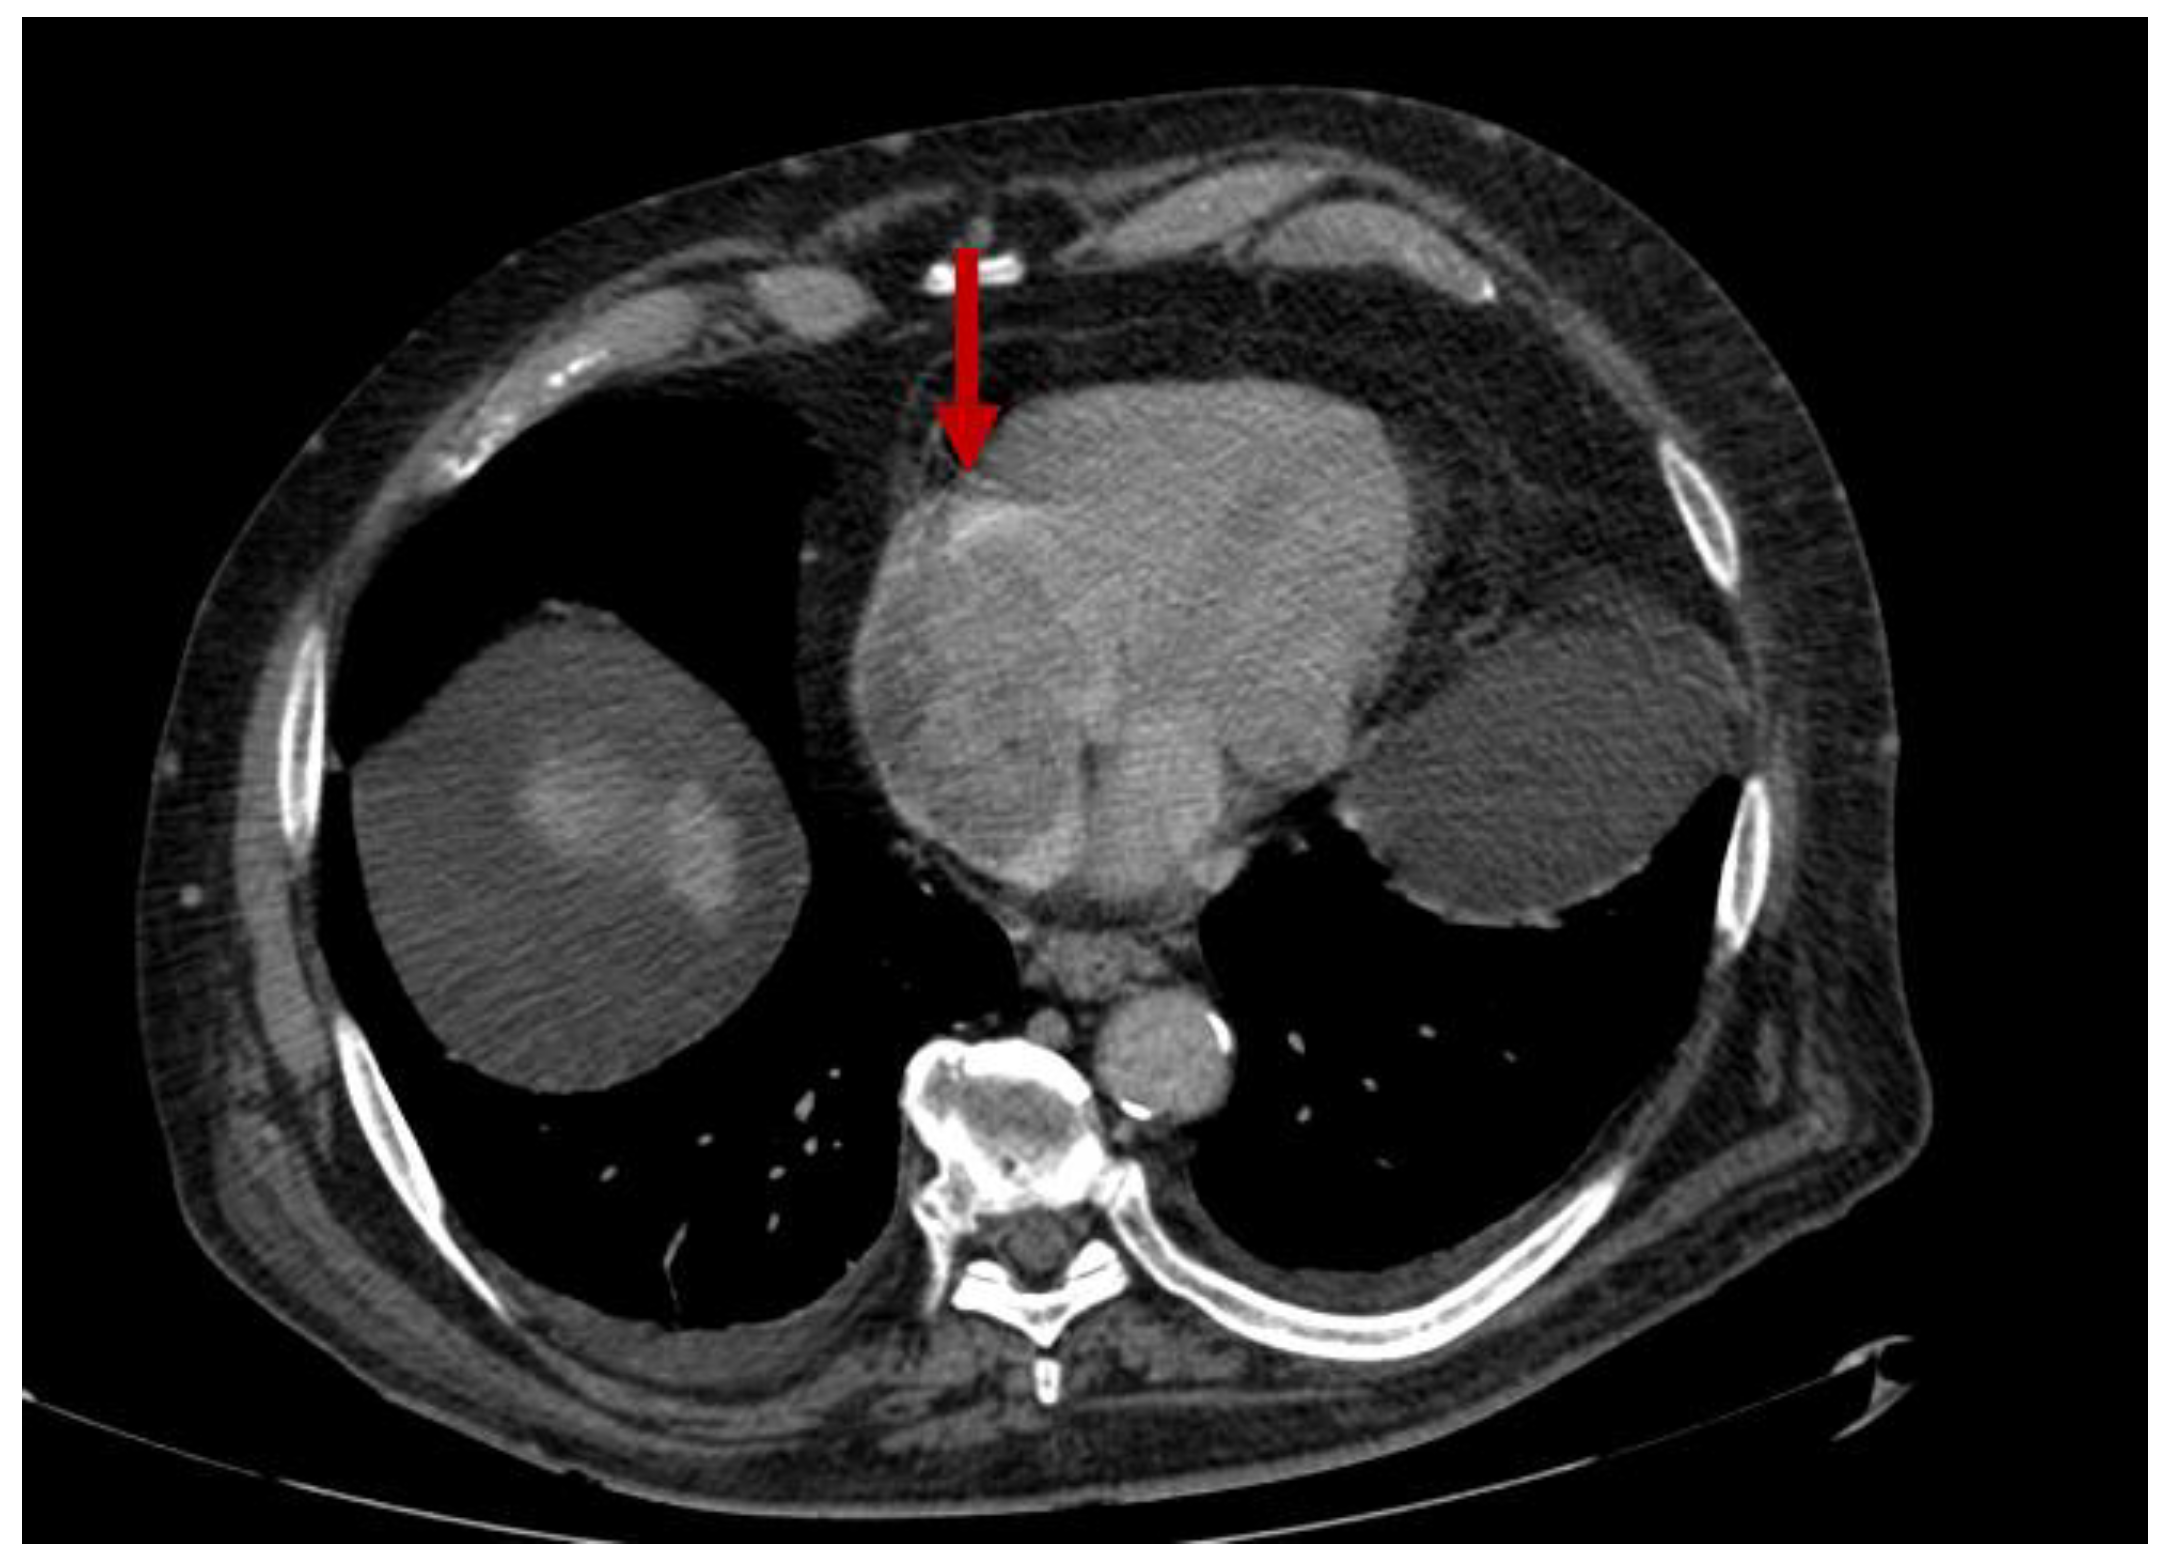

2.3. Mediastinum and Heart